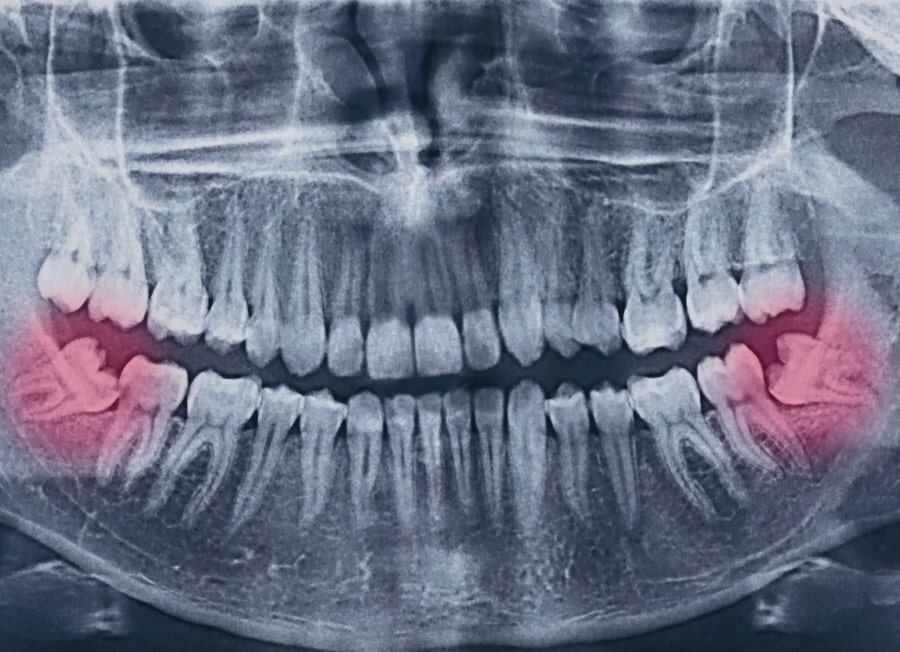

Dentists recommend tooth extractions when a tooth is severely decayed, infected, damaged beyond repair, or causing overcrowding. Dental extractions are also frequently performed for impacted wisdom teeth and as part of orthodontic treatment.

• Impacted wisdom teeth.

• Surgical dental extraction

Required for impacted, broken, or partially erupted teeth. This procedure may involve a small incision and removal of bone.